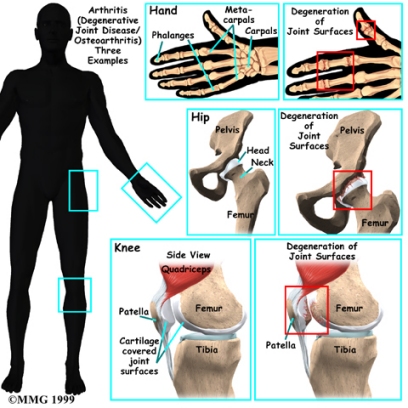

Where does OA develop?

OA is most common in the small joints of the hands, the spine, the knees, the hips, and certain toe joints. OA primarily affects the articular cartilage, the slippery, cushioned surface that covers the ends of the bones in most joints and lets the bones slide without rubbing. Articular cartilage also functions as a shock absorber.

In OA, the articular cartilage becomes damaged or worn away. As this happens, the joint no longer fits together well or moves smoothly. In the early stages of OA, the cartilage actually becomes thicker as your body tries to repair the damage. The repaired areas are more brittle than the original cartilage, and these brittle areas begin to wear away and become thin. They may even wear away entirely. This eventually leads to a condition called eburnation, in which the bones become thick and polished as they rub together. X-rays can show these changes in the cartilage and bones.

But OA is not just a disease of the cartilage. The damage to the cartilage seems to start a sort of chain reaction that involves all the parts of the joint. Bone spurs, or outgrowths, often begin to form around the edges of the joint. The joint capsule (the watertight sack around the joint) can become thickened and lose its stretch. The synovial membrane that lines the inside of the joint capsule may become inflamed (swollen, red, hot, and painful), and crystals may form in the synovial fluid. The tendons and ligaments around the joint can also become inflamed.